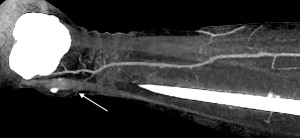

Пацієнти та методи. Відповідно до мети роботи було проаналізовано дані обстеження 46 пацієнтів, що знаходилися на стаціонарному лікуванні в опіковому відділенні КЗ «Дніпропетровська міська клінічна лікарня №2 ДОР» з глибокими локалальними ушкодженнями нижніх кінцівок в період з 2009 по 2015 рік, і яким було виконано 54 оперативних втручань із використанням локальних перфорантних клаптів з живлячою ніжкою, що включала одну домінантну перфорантну артерію. Пацієнти були розділені на дві групи. В групу 1 (контрольну) було включено 25 пацієнтів (29 оперативних втручань) у яких стандартне обстеження включало локацію перфорантів за допомогою аудіо-доплера «Мінідоп» з датчиком 8 MHz. Передбачуване місце вихода перфоранта та його напрямок позначалися на шкірі пацієнта за допомогою маркера [10,12]. (Мал. 1). В групу 2 було включено 21 пацієнта (25 оперативних втручань) у яких стандартне передопераційне обстеження було модифіковане за рахунок контрасної КТ-ангіографії [8,7] з обробкою візуальних карт судинної системи в зоні втручання програмою ”Osirix” (Мал. 2).

Мал. 2. Контрасна КТ-ангіографія з обробкою візуальної карти судинної системи нижньої кінцівки в зоні втручання програмою ”Osirix”. Точку виходу перфрантної артерії в шкіру над кісточкою – відзначено стрілкою.